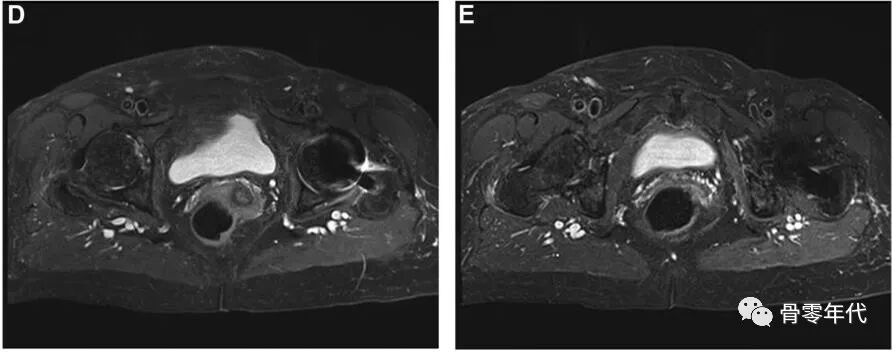

(A-C)术前X光显示先前植入的右侧全髋关节假体,包括非骨水泥的股骨柄和非骨水泥的髋臼假体。(D和E)外展肌重建后12个月MRI图像显示臀中肌、臀小肌、臀大重建瓣和阔筋膜张肌重建瓣完整。患者报告的外展肌重建术22个月的结果包括:静息疼痛,1/10;行走疼痛,3/10;Harris髋关节评分,58;牛津髋关节评分,23。病人报告说,走路时有轻微的跛行和拐杖。